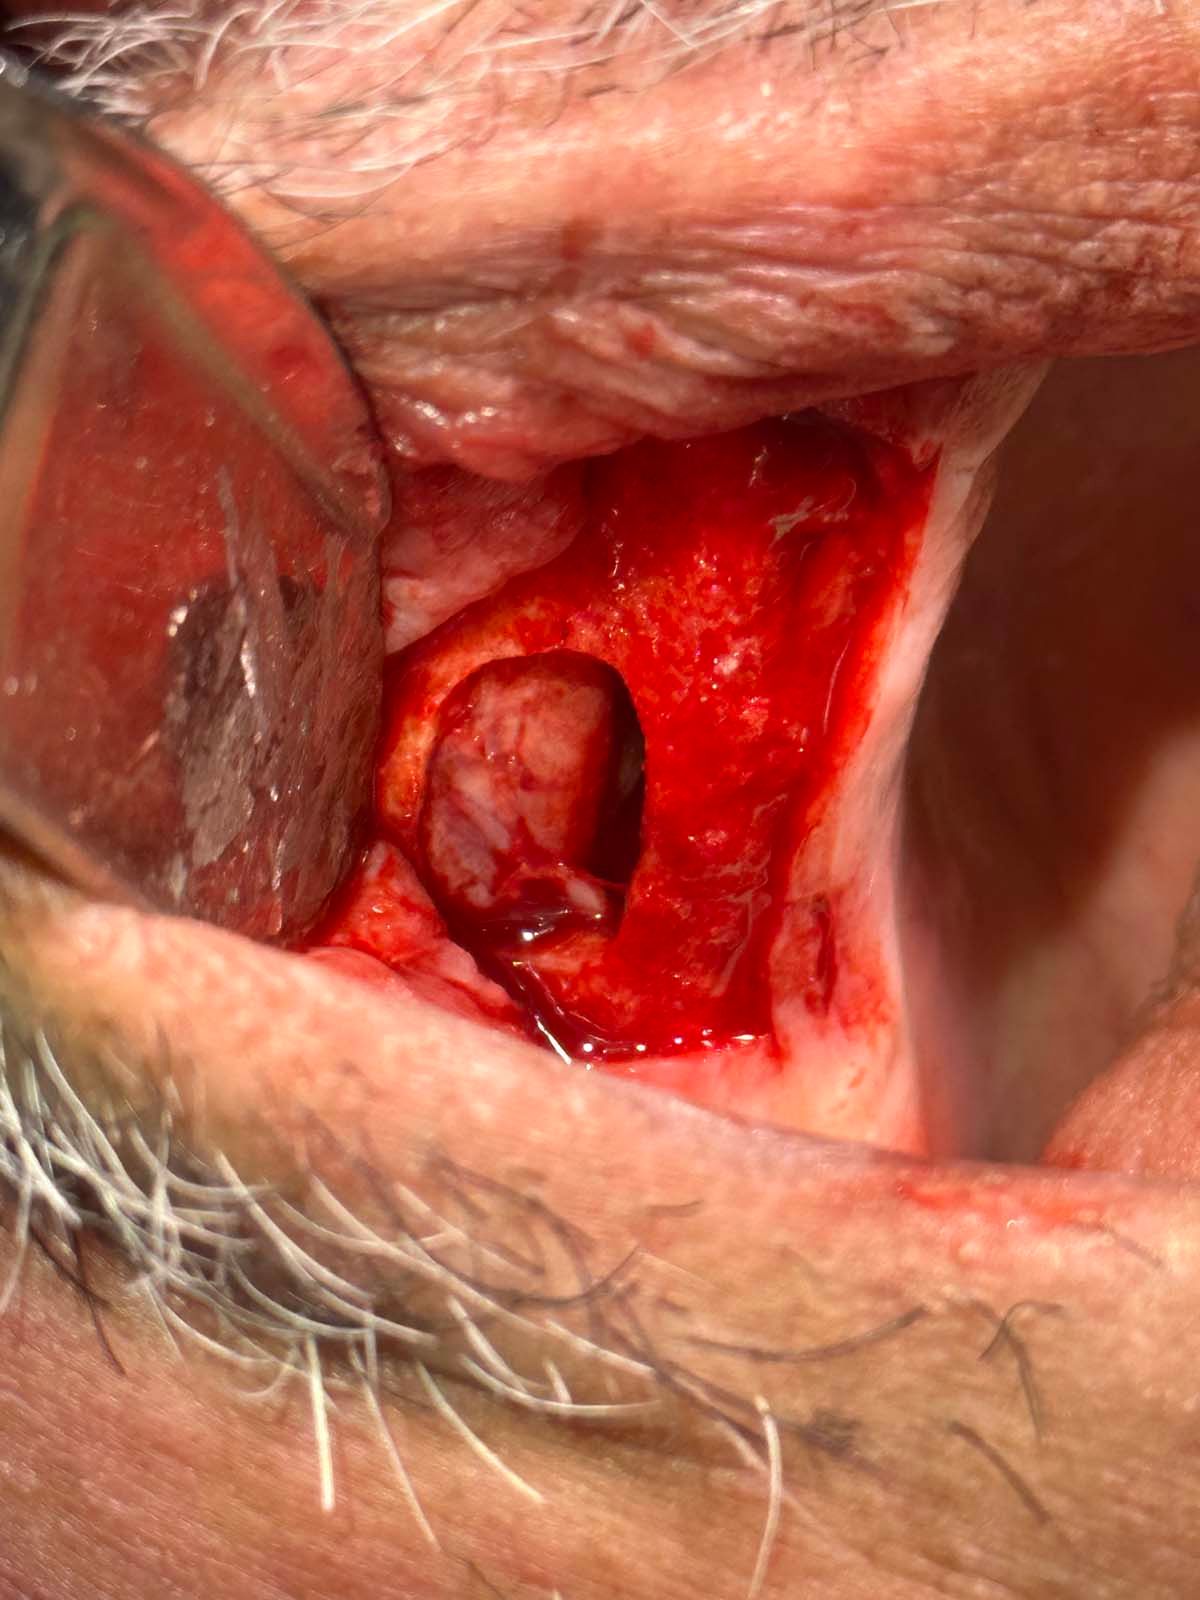

Infection was identified on pariapical x-rays.

A look at patient's periapical x-rays.

The CBCT revealed the extent and solidified the opportunity to make the correct clinical decision